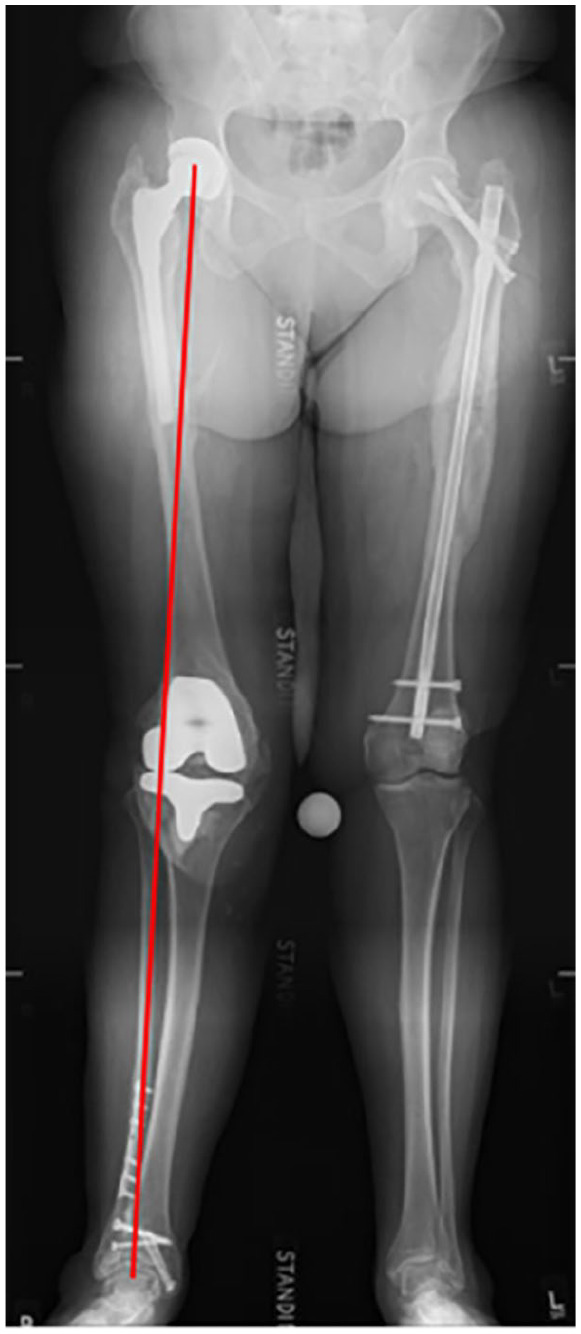

Background: Total knee arthroplasty (TKA) and hindfoot reconstruction (HFR) are often used to treat osteoarthritis and deformities of the knee and hindfoot. Despite the proven clinical effectiveness of these treatments, postoperative patient dissatisfaction is high. The knee and ankle are adjacent joints in the lower extremity, and angular deformity of either joint is known to affect positioning of the anatomical and mechanical axes of the entire limb. Although it is understood this relationship exists, there are limited studies evaluating outcomes of ipsilateral procedures on patients with pathologies of both knee and hindfoot. This article aims to evaluate whether TKA or TAA/HFR sequencing influences postoperative outcome. The study hypothesis is that TKA prior to TAA/HFR results in lower reoperation.

Abstract Image